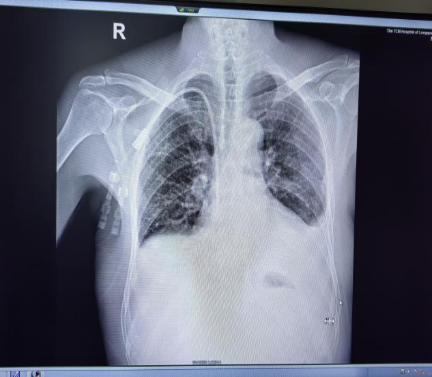

患者胡先生,因全身重度水肿3月于我院肾病科住院治疗,诊断为:

“慢性肾脏病5期、急性心力衰竭、肾病综合征、腹腔积液、胸腔积液”等。

经临床诊治后,建议患者建立长期血液透析通路,维持血液透析治疗。为了保障患者的生命安全并提升透析治疗质量,肾病科王文平主任立即组织了全科医生对胡先生的病例进行了病情讨论。

综合考虑胡先生的具体情况,并与家属充分沟通后,肾病科团队决定解决为肾透析的血管通路问题,采用超声引导下穿刺颈静脉联合DSA技术引导,在右侧颈内静脉置入带隧道带涤纶套的中心静脉透析导管置管术。

手术十分成功,血流通畅,术后血液透析顺利,达到了为肾透析的血透通路的要求。